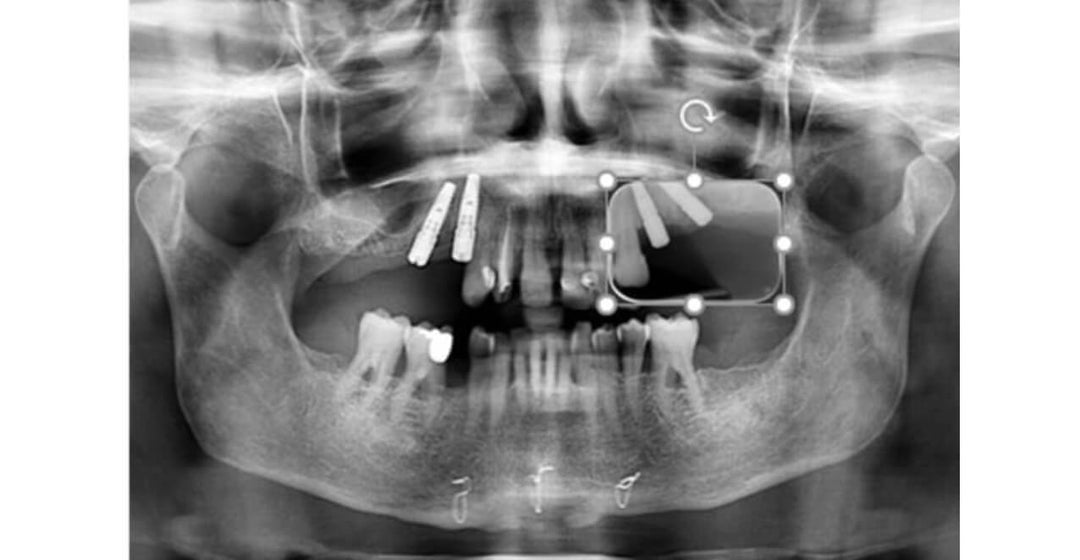

DIGITAL WAX UP BRIDGE APPLICATION

There are million of crowns and bridges fabricated all over the world in a year. As this number increases, the traditional method is becoming more and more expensive, so cost-efficiency is a key. SHINING3D is excited to introduce a more...

Step 1: Photographic Data Collection Step 2: Data collection with Face scanner and intraoral scanner Step 3: DSD and Model Creator Step 4: Temporary crowns and model printing Step 5: Try-in of the temporary veneers Step 6: Tooth preparation Step...